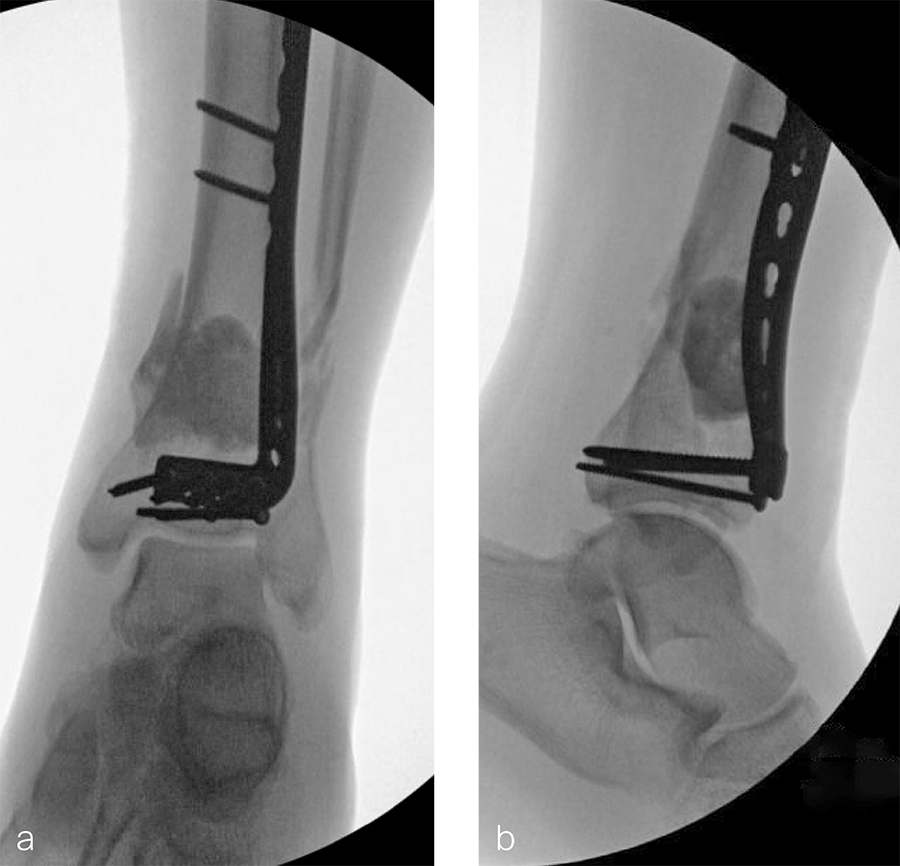

The patient was discharged on hospital day 6 to a rehabilitation facility with his left lower extremity in a splint and touch down weight bear allowance. He returned 2 weeks later with drainage from the medial traumatic wound. In addition, he had a gastrointestinal bleed from use of nonsteroidal antiinflammatory drugs. Once the gastrointestinal bleed was stabilized, he was taken the next day to the OR for another incision and drainage. Further, more significant, devitalized bone was resected, and an antibiotic cement spacer was placed (Fig 3). Deep culture samples were taken despite knowing the antibiotic resorbable beads had been placed in the wound at the time of initial closure. The plate was left in place, but a planned exchange plate/nailing was to be performed pending final culture results.

Cultures eventually yielded Klebsiella pneumoniae and Enterobacter cloacae. The patient was administered intravenous antibiotics for 6 weeks and was discharged home with therapy and nursing. He returned to the clinic with wound breakdown and an exposed cement spacer at 10 weeks after injury. Further bone debridement, spacer exchange, repeated culture samples, and plastic surgery were undertaken to help with wound coverage with a rotational flap. The microbiological culture was still positive for Klebsiella pneumoniae.

Two months later, the patient had a staged cement spacer removal and hardware removal followed by a new spacer placement (Fig 4). When microbiological cultures were negative for 5 days he was taken to the OR for definitive fixation and bone grafting. RIA bone graft from the ipsilateral femur was taken, a new anterior lateral plate was placed with an adjunct IM nail (and angle stable screws) as the distal plafond was now one articular block (Fig 5).